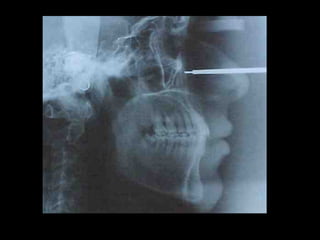

Cefalometría elementalCefalometría elemental

Deflección craneal 26º

Longitud craneal anterior 59 mm.

Altura posterior facial 59 mm.

Posición de rama mandibular 78º

Localización de Porión 38 mm.

Arco mandibular 30º

Longitud de cuerpo mandibular 81 mm.

Deflección craneal 26º Longitudcraneal anterior 59 mm. Altura posterior facial 59 mm. Posición de rama mandibular 78º Localización de Porión 38 mm. Arco mandibular 30º Longitud de cuerpo mandibular 81 mm. Deflección craneal 26º Longitud craneal anterior 59 mm. Altura posterior facial 59 mm. Posición de rama mandibular 78º Localización de Porión 38 mm. Arco mandibular 30º Longitud de cuerpo mandibular 81 mm.